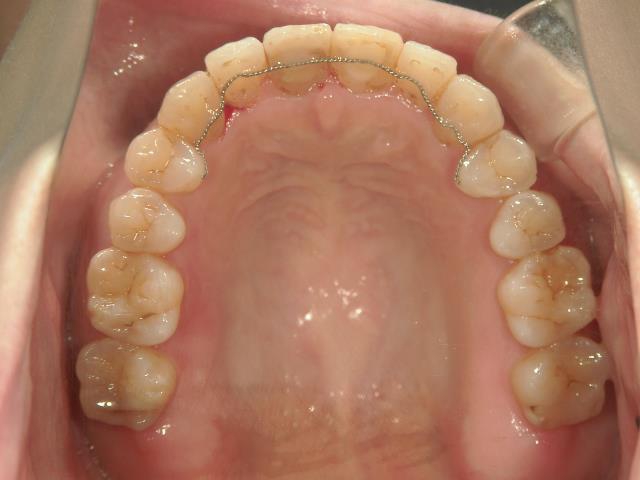

矯正歯科 治療後矯正歯科 プチワイヤー矯正 治療後矯正歯科(プチワイヤー矯正)治療後

矯正歯科 治療後  スペース確保の為、 2番抜歯

矯正_灰色.pngno.37_7548_治療後_上.JPG矯正_灰色.png